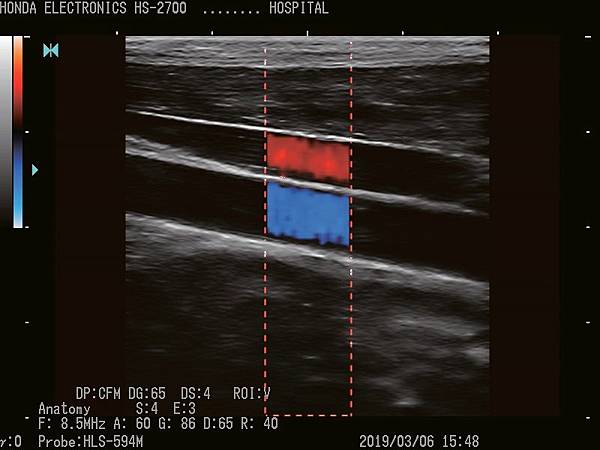

HS-2700支持CFM(彩色血流向)和PD(功率杜普勒)模式。

它們將適應廣泛的醫療應用。